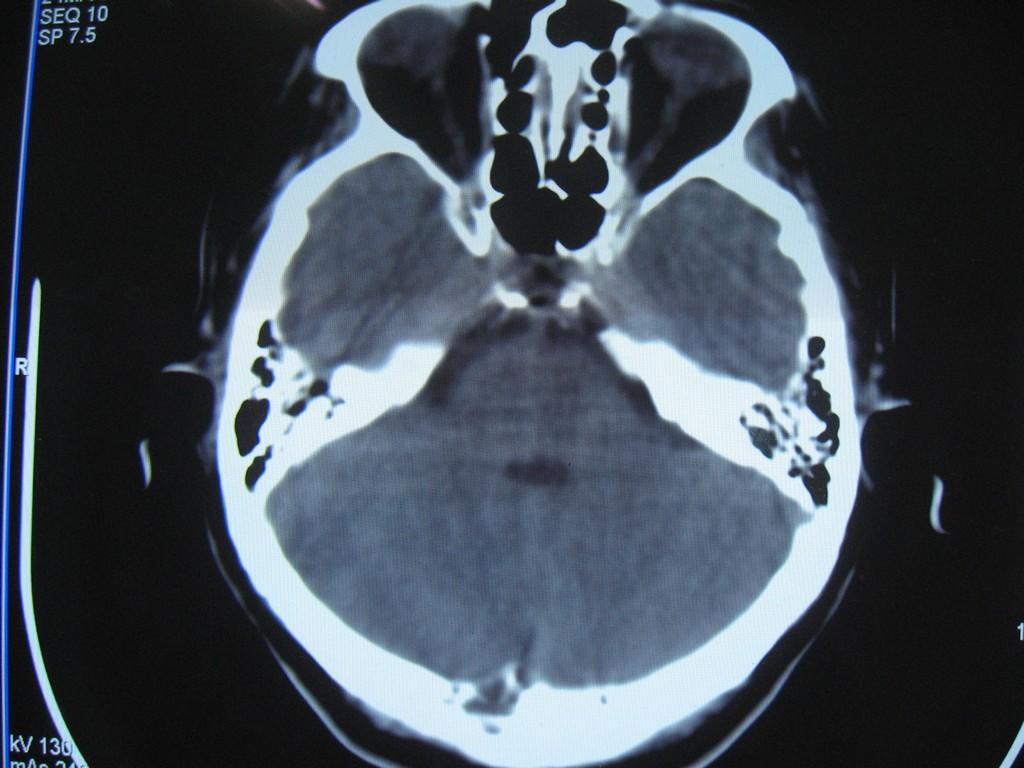

标题: CT22032B:枕骨破坏(从新调整窗宽窗位) [打印本页]

标题: CT22032B:枕骨破坏(从新调整窗宽窗位)

女性病人,53岁,偶尔感枕部针刺样疼痛,ct扫描如下。

蛛网膜颗粒压迹。鉴别:骨巨,嗜酸性肉芽肿,骨髓瘤。

蛛网膜颗粒压迹。

骨巨,嗜酸性肉芽肿,骨髓瘤,动脉瘤样骨囊肿可能

支持蛛网膜颗粒压迹。

支持蛛网膜颗粒压迹,鉴别:骨巨,嗜酸性肉芽肿,骨髓瘤、转移瘤

支持蛛网膜颗粒压迹,嗜酸性肉芽肿发生于30岁以下,基本排除,骨髓瘤、转移瘤多伴有软组织肿块,范围较广。

枕骨蛛网膜颗粒压迹。